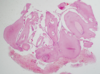

what are the different patterns of histopathology in ameloblastoma

follicular or plexiform

describe the follicular pattern of histopathology in an ameloblastoma

- rounded islands or follicles

- surrounded by fibrous tissue

- resembling enamel organ of tooth germ

- central mass resembling stellate reticulum

- periheral layer resembling ameloblasts

- nuclei of peripheral cells show reverse polarity

describe the plexiform histology of an ameloblastoma

- tangled network of

- anastamosing strands

- irregular massess

- peripheral layer of ameloblast like columnar cells with central stellate reticulum like cells

- cyst formation common but due to stromal degeneration